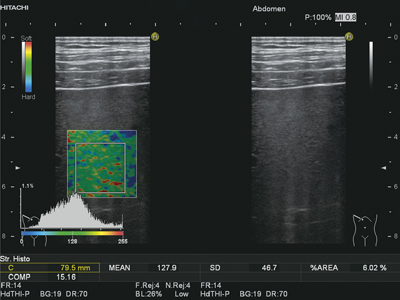

■Strain Histogram計測

Strain Histogram計測は,ROI内の任意に指定された領域の相対歪み値のヒストグラム(頻度分布のグラフ)を表示する(図3)。また,テクスチャー解析を行うことで,Elastography画像の特徴量を算出する。

これにより,より客観的な評価が可能となることが示唆されており,肝臓領域などでの有用性が期待されている。

図3 Strain Histogram計測